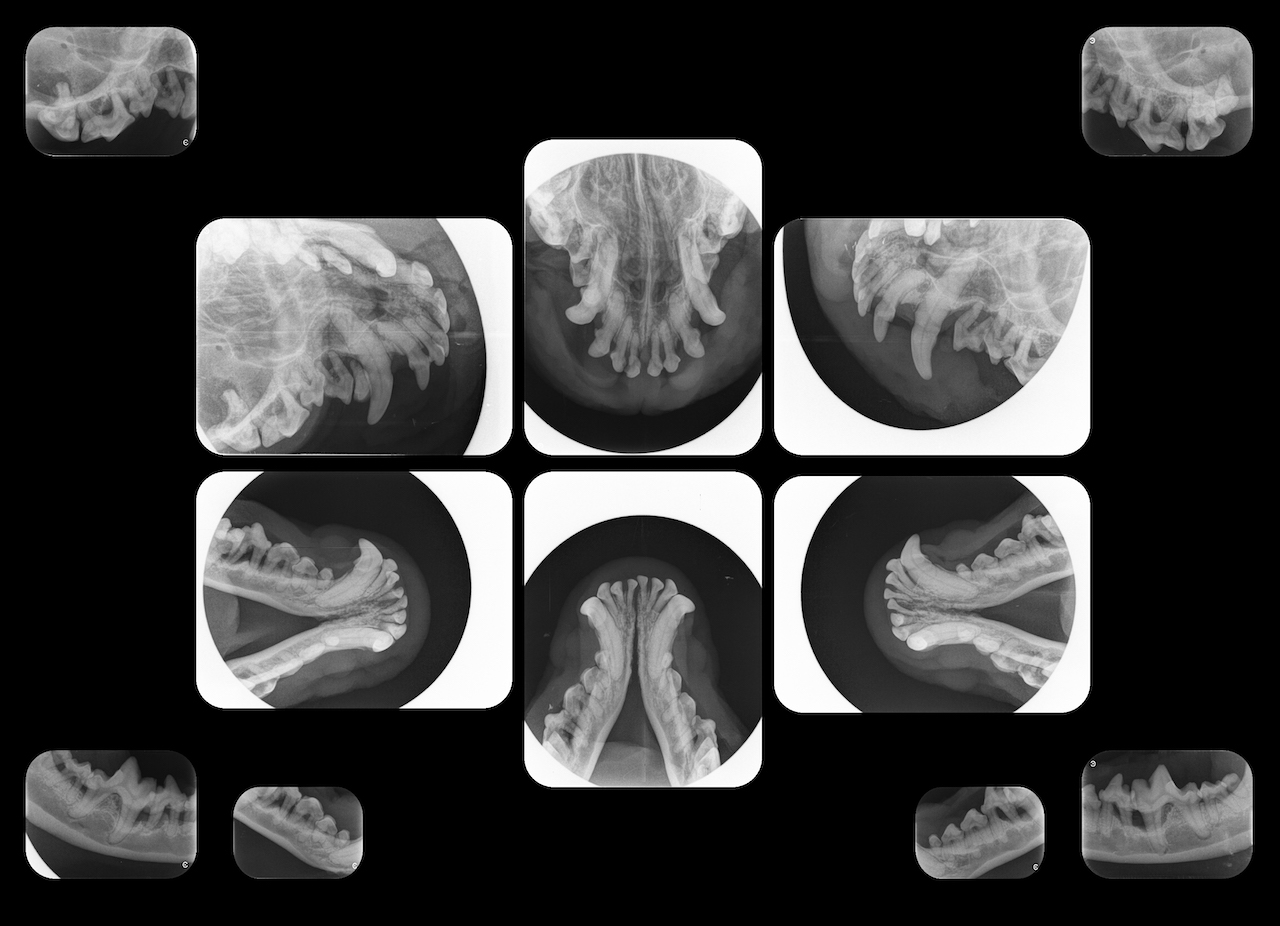

- The principles of intraoral radiography, and the correct use of radiology equipment and techniques to obtain and interpret diagnostic quality intraoral radiographs, including a full-mouth series

- How to interpret diagnostic-quality intraoral radiographs, including a full-mouth series

Dental diseases are among the most common diseases in small animals. Most occur below the gumline, and thus aren’t readily visible without radiographic assessment.

The current standard of care requires imaging as a part of routine dentistry, but the purchase of dental X-ray equipment for your practice is a substantial investment. Ensure that it doesn’t go to waste by enrolling your team in our dentistry diagnostics course.

There is something in this program for every veterinary professional at your practice. In addition to learning about dental anatomy and disease processes, technicians will be able to properly set up patients to obtain the highest quality radiographs. Your veterinarians can go in depth to understand the interpretation of radiographs, as well as examinations under anesthesia.